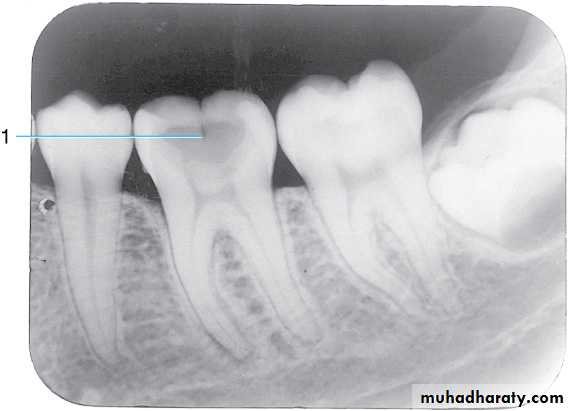

Radiograph of mandibular molar area. Shown are the (1) oblique ridge (buccal), (2) mylohyoid ridge (lingual) (3) mandibular canal, and (4) submandibular fossa

Radiograph of mandibular molar area. Shown are the

(1) Ext oblique ridge,(2) mylohyoid or internal oblique ridge,(3) mandibular canal and

(4) submandibular fossa